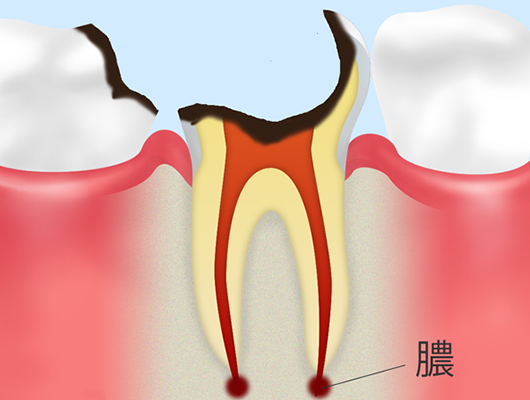

神経にまで達したむし歯(C3)象牙質のさらに奥にある神経(歯髄:しずい)にまでむし歯が進行した状態です。この段階になると冷たいもの以外にも熱いものがしみたり、場合によっては何もしなくてもズキズキとした激しい痛みをともなったりします。また治療では神経を取り除く治療(根管治療)が必要です。 |

歯の根っこしか残っていないむし歯(C4)むし歯によって歯質の多くが破壊され、歯ぐきの中に根っこだけが残っている状態です。神経も死んでしまっているため、痛みを感じることはありません。この状態にまで放置してしまうと歯を残すことが難しく、抜歯となるケースが多くなります。 |